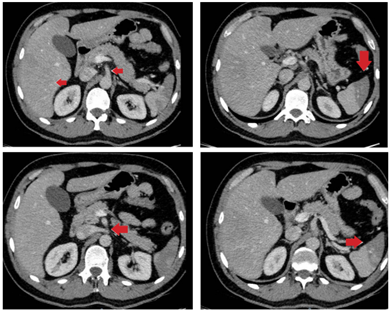

Por la persistencia del dolor se solicitó una tomografía computarizada contrastada de abdomen para descartar patología inflamatoria, encontrando múltiples infartos esplénicos y trastorno de la perfusión hepática, con aparente origen en un defecto de llenado lineal del tronco celíaco (figura 1). De manera consensuada con radiología se solicitó una angiotomografía para esclarecer la lesión vascular, encontrando una disección contenida del tronco celíaco y autolimitada a la arteria hepática común, después del origen de la arteria gástrica izquierda y antes del origen de la arteria gastroduodenal, sin presencia de aneurismas. No se encontró compromiso isquémico de las vísceras (figura 2).